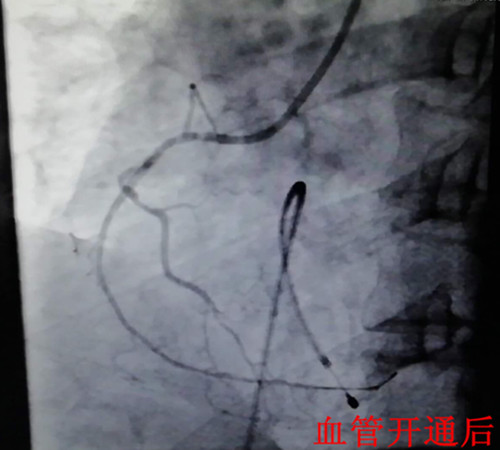

在一陣有效地?fù)尵戎?,患者在氣管插管、呼吸機(jī)輔助呼吸下,先行心臟臨時(shí)起搏器置入,后行左右冠狀動(dòng)脈造影,造影顯示:右冠狀動(dòng)脈呈鼠尾狀,開(kāi)口5mm處100%閉塞,旋支血管中遠(yuǎn)段60—99%彌漫狹窄病變。手術(shù)者立即開(kāi)通右冠狀動(dòng)脈,盡管患者在手術(shù)過(guò)程中不斷出現(xiàn)室速室顫,血壓下降,但隨著右冠狀動(dòng)脈遠(yuǎn)端血流恢復(fù),患者終于生命體征趨于平穩(wěn),安全返回監(jiān)護(hù)室繼續(xù)下一步治療。